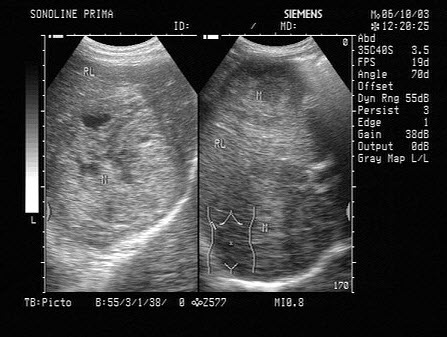

15、单项选择题

某患者收缩期超声心动图所示,提示()

A.二尖瓣狭窄

B.二尖瓣关闭不全

C.房间隔缺损

D.动脉导管未闭

E.以上都不是